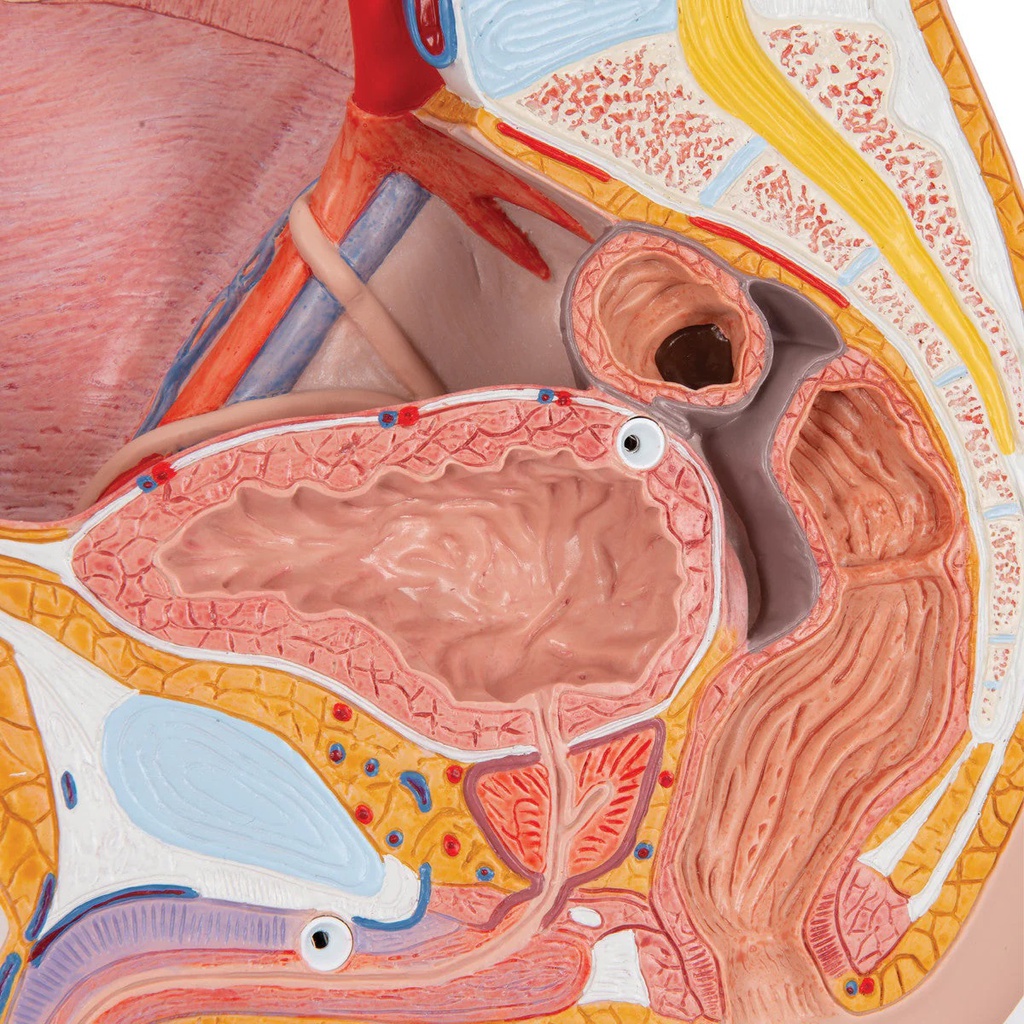

Male pelvis model in median section, 2 part

The male pelvis anatomy model is shown in median section. One half of male genital organs with bladder is shown at the normal position in the male pelvis. The rectum is removable for a more detailed study of the male pelvic anatomy. This high quality anatomy model is delivered on baseboard offering the possibility to be mounted to the wall.